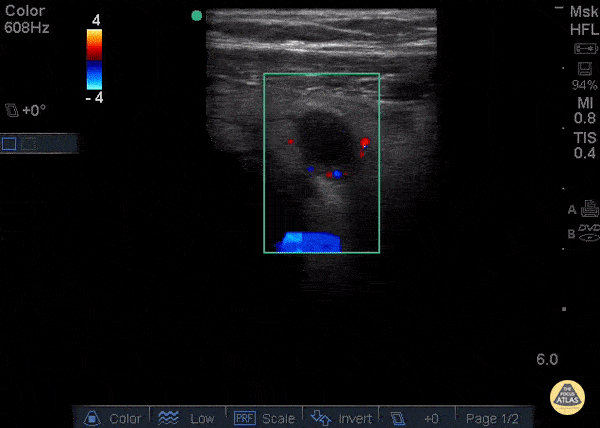

Ring of Fire - Increased vascularity visualized using color-flow Doppler known as "Ring of Fire."